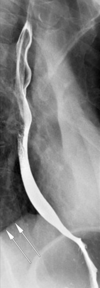

23

Q

A

aortic arch makes this indentation in the oesophagus